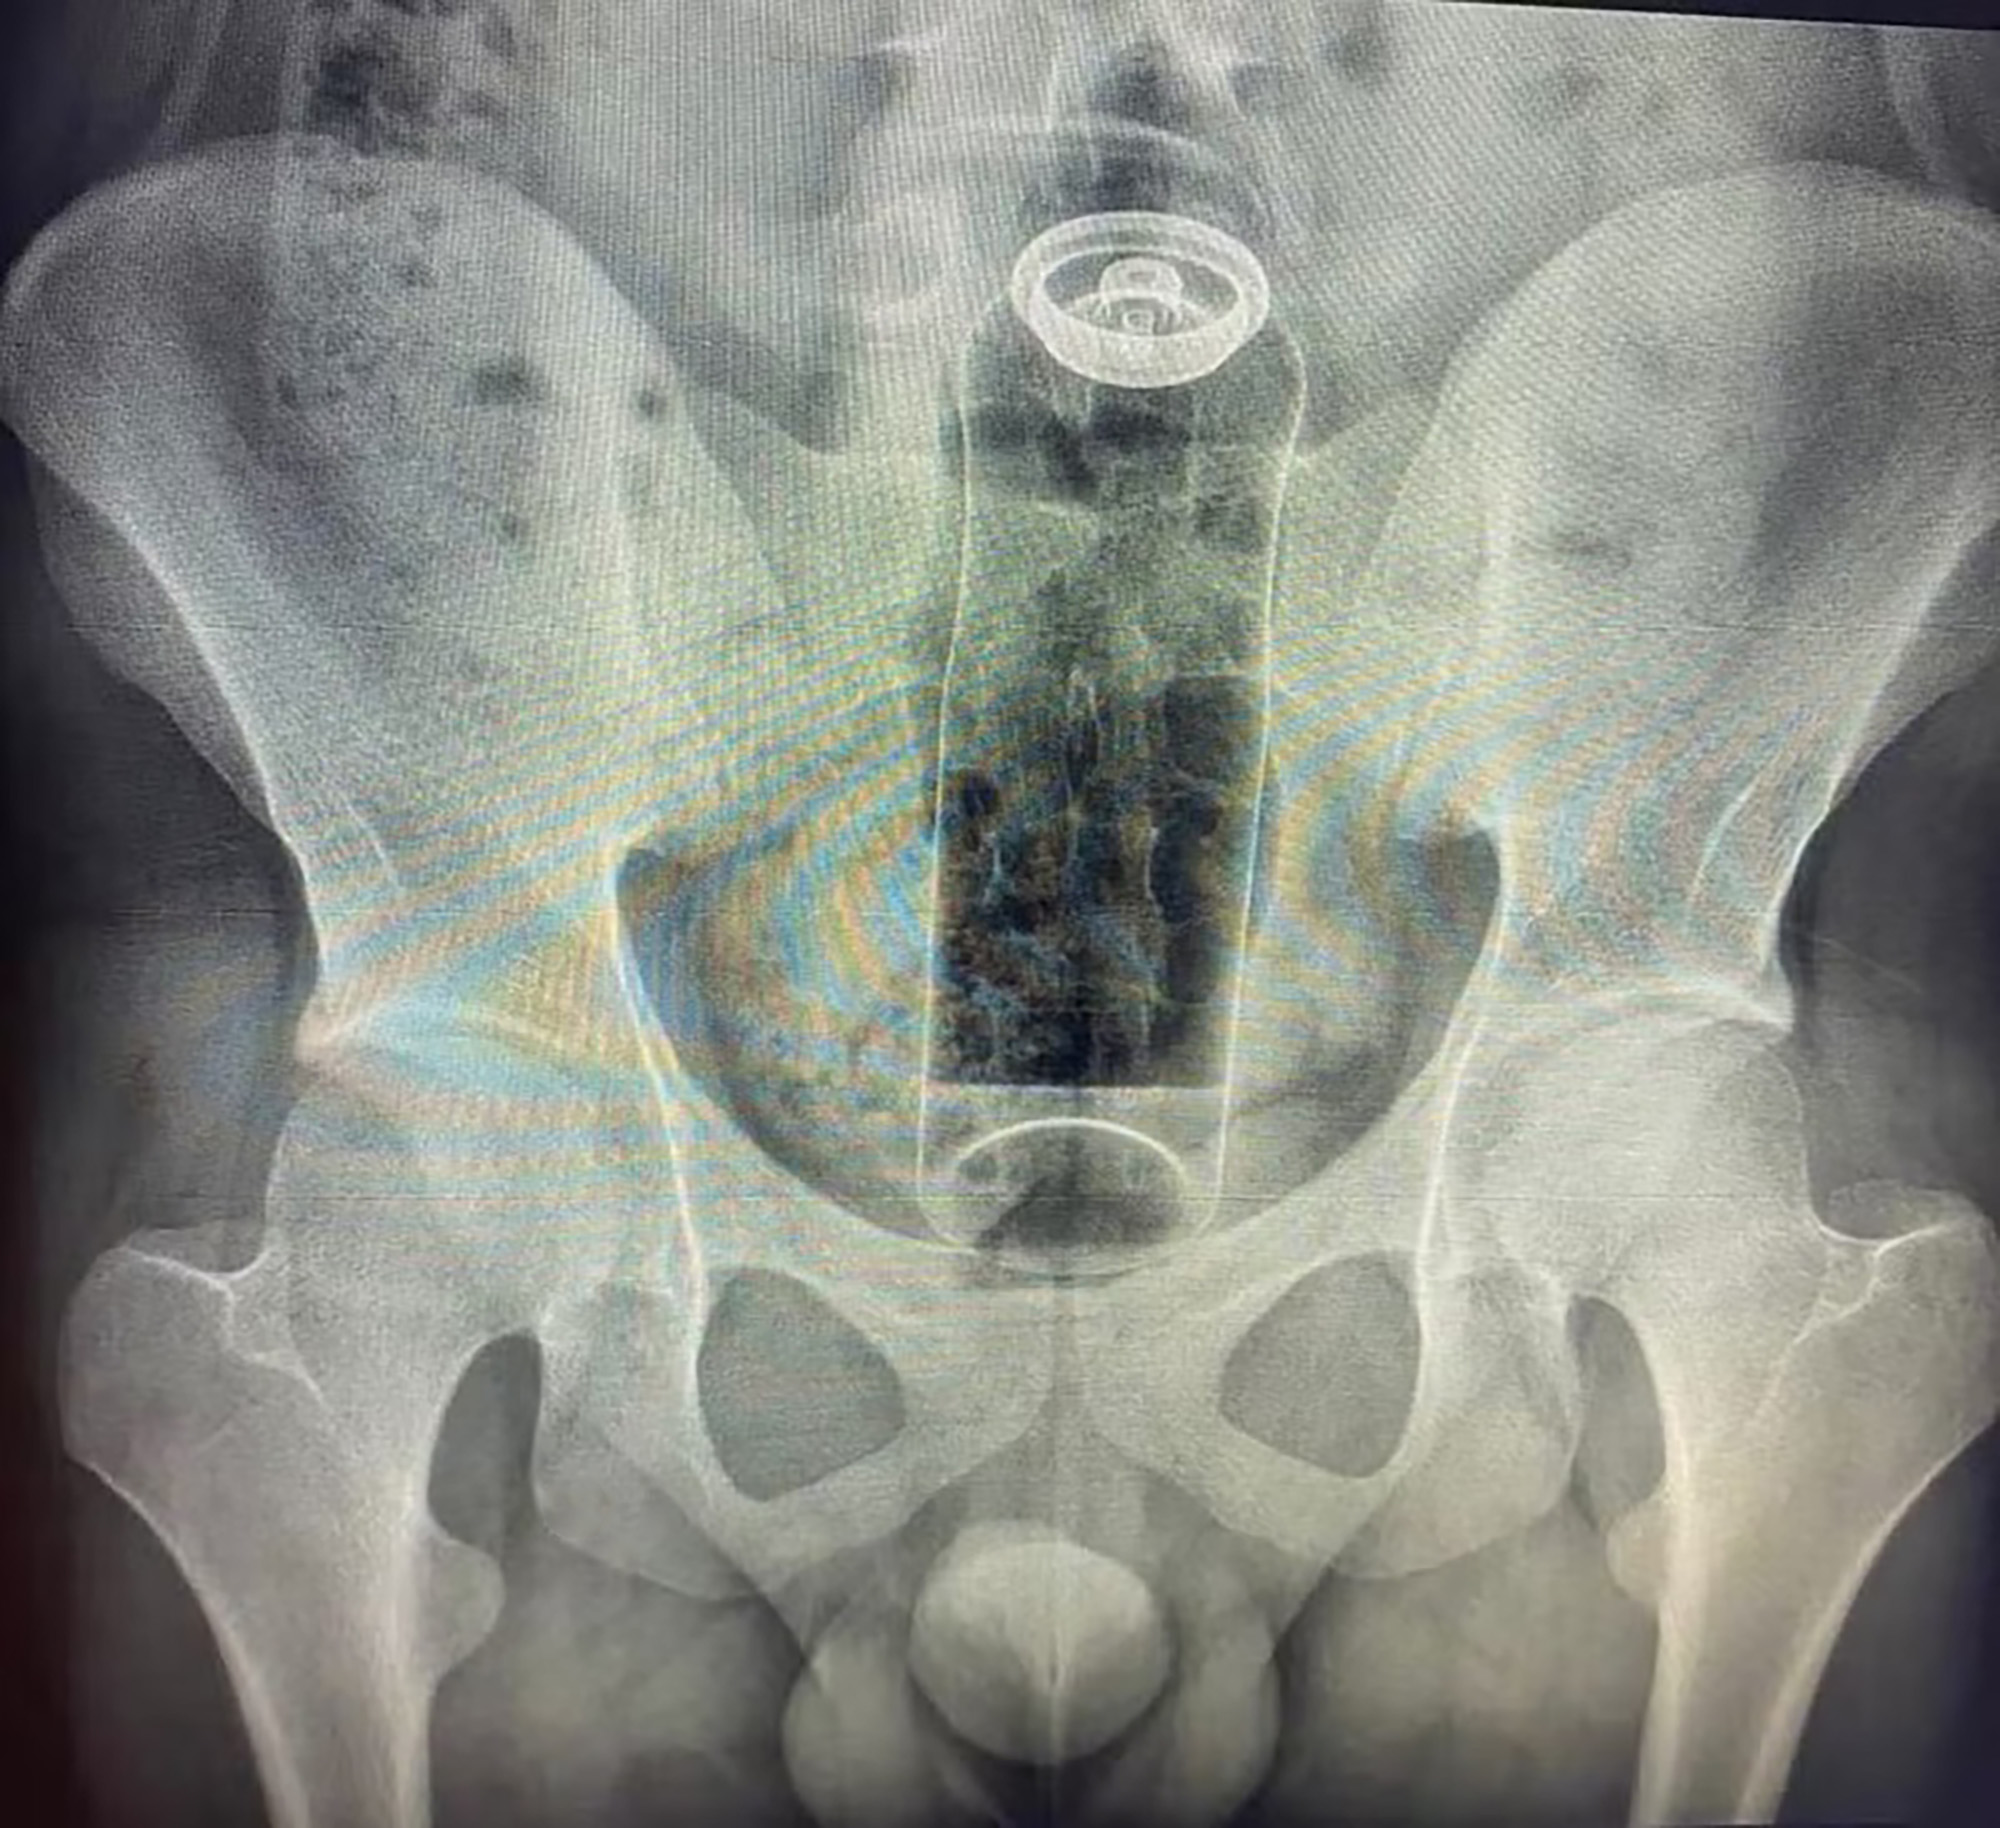

An x-ray image shows the deodorant stuffed in the bum, undated. A 19-year-old patient had inserted the item during a sexual game. Note: Private photo. (Newsflash)

A 19-year-old man had to be rushed to hospital after a deodorant container became stuck inside his rectum and could not be removed.

The patient, who was not named, was admitted to hospital in Sao Paulo, Brazil, with intense pain and abdominal discomfort after he inserted the deodorant during a "sexual game", local media reported on 26th January.

According to colorectal surgeon Daniel Brosco, the object moved further up and got lodged in the patient's rectum.